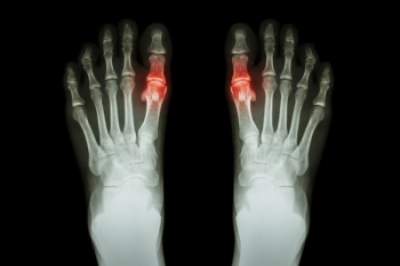

While providing a variety of treatments for various foot and ankle conditions, we also specialize in conservative and surgical approaches to all foot and ankle pathology.

Skip your trip to the Emergency Room and let us treat all your foot and ankle pathology. X-rays on premises.